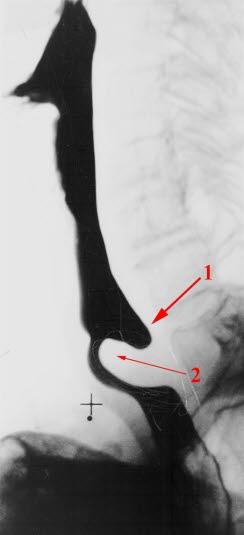

Zenkers divertikkelFor å få bekreftet at du virkelig har utposninger på spiserøret, må du på sykehuset for å ta røntgenbilder. Divertiklet fremstilles både forfra og fra siden etter nedsvelging av bariumkontast. Det fremstilles best under svelging og ses særlig på sidebildene. I noen tilfeller vil det også være nødvendig å kikke ned i halsen din med et gastroskop (en bøyelig, fingertykk slange legen kan se gjennom).